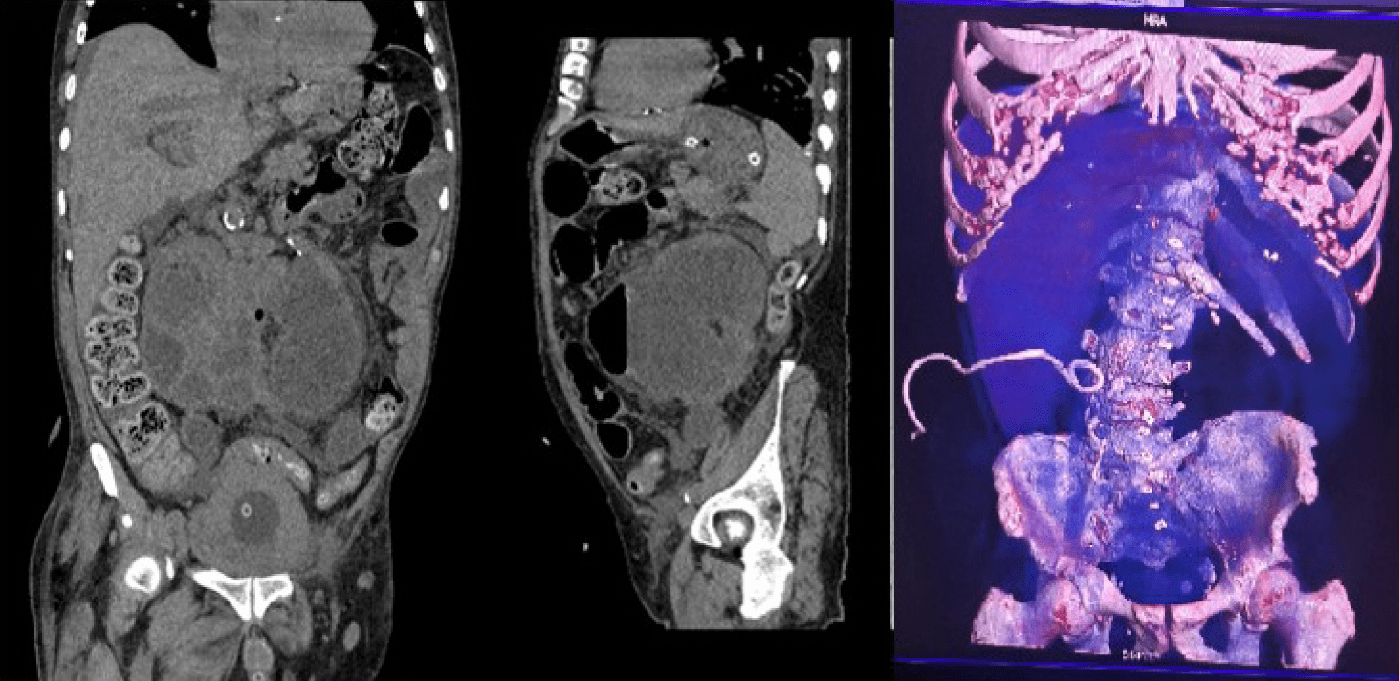

Se tomó inicialmente serie abdominal de rayos X, en la que presentan asas intestinales distendidas con nivel hidroaéreo sin lograr observar gas distal (Figura 1). El ultrasonido no fue concluyente debido a la interposición de gas que limitaba ventana acústica.

Serie abdominal presenta asas intestinales distendidas con nivel hidroaéreo sin gas distal

Figura 1